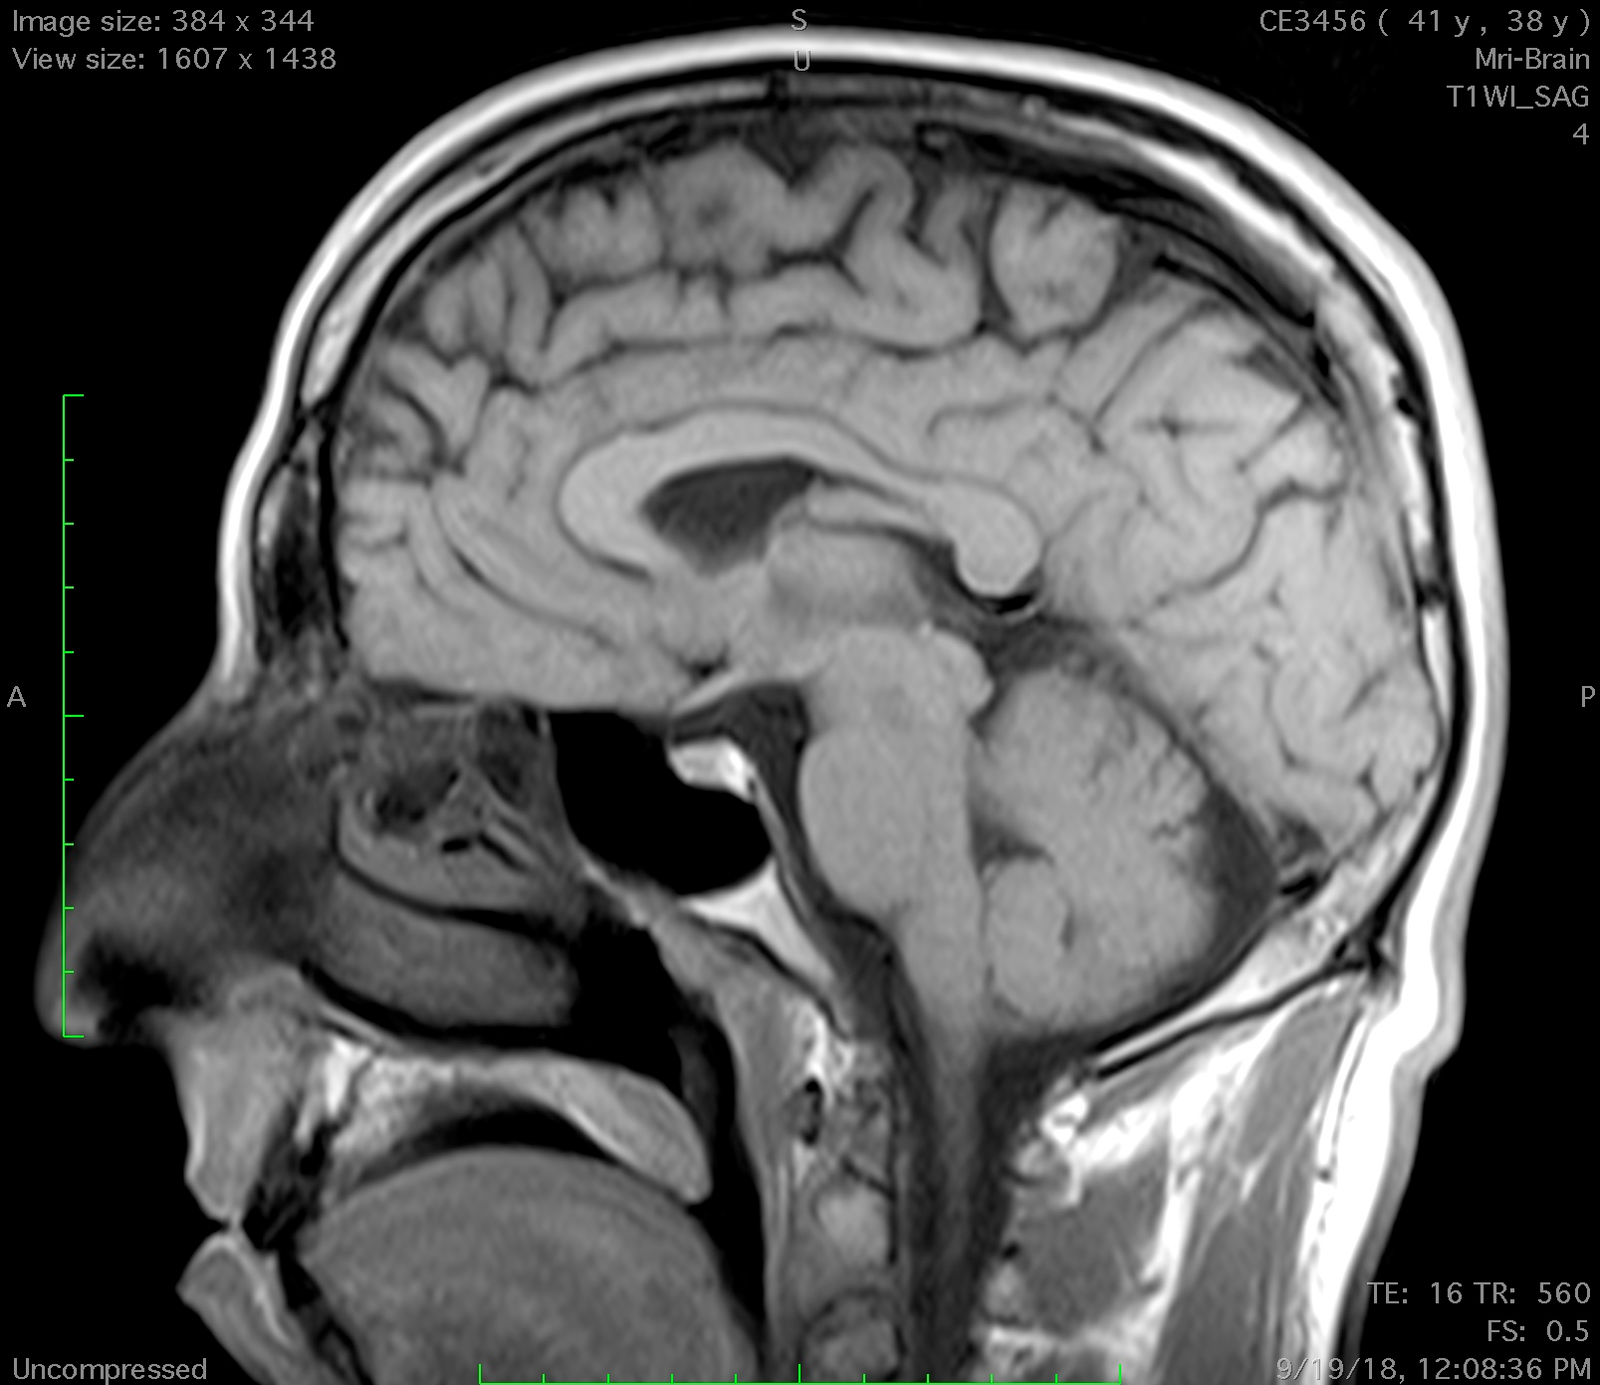

Clinical Images